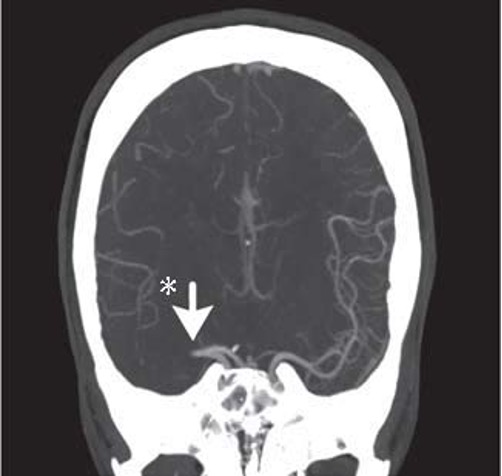

CT angiogram is useful in identifying LVO to select patients who may be candidates for endovascular therapy. This could be useful in patients with a high NIHSS = 7-10 to evaluate for LVO and 11-14 may require thrombectomy. It helps determine how accessible the clot is. Not all centers do these routinely on all stroke patients. More than the risk of renal injury (0.04%) is the risk of allergy.

Multiphase CTA has three sets of pictures: an arterial, venous (8s later) and late venous phase (16s later) to check for collateral circulation, important in prognosis.